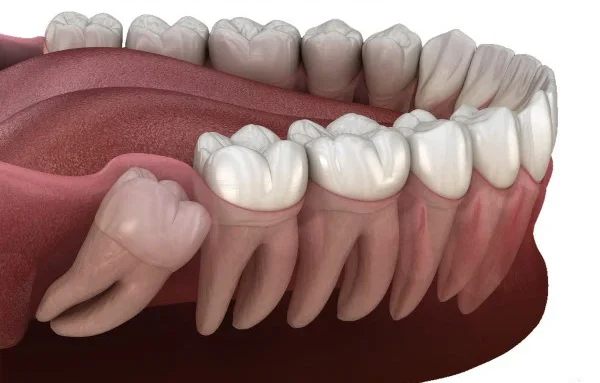

Safe and Efficient Removal of Impacted Wisdom Teeth

Wisdom teeth, also known as third molars, often emerge between the ages of 17 and 25. While some individuals may have no issues with their wisdom teeth, others may experience problems such as impaction, overcrowding, or infection. At Vitalis Dental, we specialize in the safe and efficient removal of wisdom teeth to prevent and address these complications.

With modern anesthesia and our gentle techniques, wisdom teeth removal is virtually painless. Most patients experience minimal discomfort during and after the procedure, which can be managed with over-the-counter pain relievers.

Recovery time varies depending on the complexity of the extraction. Generally, it takes about one to two weeks for the initial healing, during which you should follow our post-operative care instructions to ensure proper healing and prevent complications.